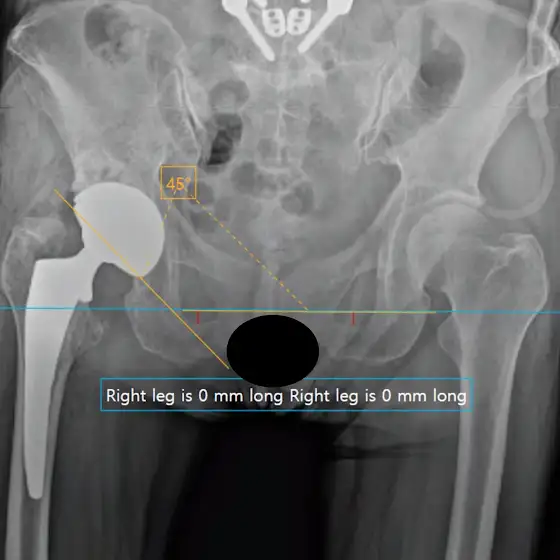

평촌서울나우병원 고관절 인공관절 수술에 컴퓨터 내비게이션을 도입하여 사용하기 시작했습니다. 장비는 Johnson & Johnson MedTech의 Velys Hip Navigation입니다.

이전 영상에서 아직은 인공관절 수술에서 로봇의 도움은 저에게는 필요하지 않다고 말씀드린 적이 있지만, AI의 도움을 받는 컴퓨터 내비게이션은 수술 전 계획을 세우는데 매우 편리하고, 수술 중 다리 길이나 임플란트의 크기, 각도를 측정해서 정확성과 정밀도를 높이는데 매우 유용합니다.

그리고, 수술 후 사진을 분석하여 세번째 사진에서 보시는 바와 같이 다리 길이 차이가 0mm 측정되는 것을 확인할 수 있는 등 지금까지도 훌륭한 결과를 보이고 있는 고관절 인공관절 수술을 보다 더 정밀하고 정확하게 시행할 수 있는데 큰 도움이 될 것으로 기대됩니다.